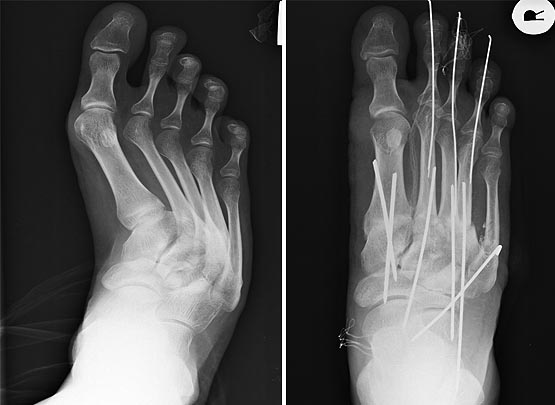

Полностью поддерживаю вопрос господина Бережного и в качестве

иллюстрации предлагаю вот такое изображение.